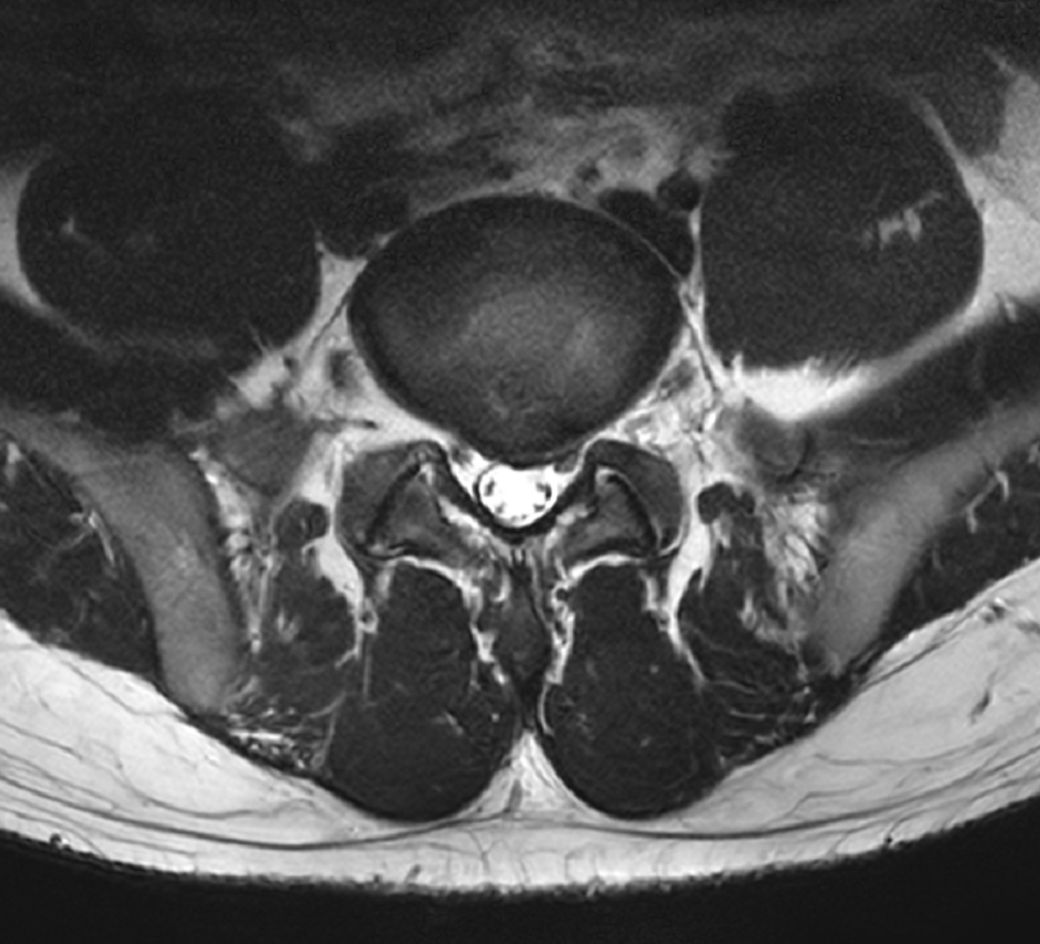

허리 삐끗후 mri 촬영하여 cd만 받고 진료는 좀 뒤로 밀려서 궁금한 마음에 사진 올립니다 ㅜ

먼저 cd 열어보니 사진이 여러개 있던데 대충 사진 보는 법 구글링해서 몇개 추출한거라 단면 같은건 잘못된 걸 고른걸 수도 있어서 양해 부탁드립니다 ㅜ

1. 현재 평소에는 큰 통증은 없지만 오래 걷거나 앉으면 허리가 뻐근해집니다... mri상 상태가 많이 심각한가요?

2. 한국나이로 27살인데 진로 준비로 고등학생때부터 앉아있는 시간이 정말 긴편이라 약간의 허리통증은 항상 있었습니다. 현재 나이에 비해 퇴행성 변화?는 많이 심각한가요? 3~40대에 심각하게 아플까봐 걱정입니다 ㅜ

요추5번 - 천추1번 사이의 디스크에 탈출증이 있으시네요.

나이에 비해서 디스크간격도 좀 좁아져있는 상태입니다. 지금 허리가 아프신것도 다 디스크가 원인이겠습니다.

이야기 하신것과 같이 오래 허리를 굽힌 상태로 앉아있는 생활이 이 디스크탈출의 원인이겠습니다.